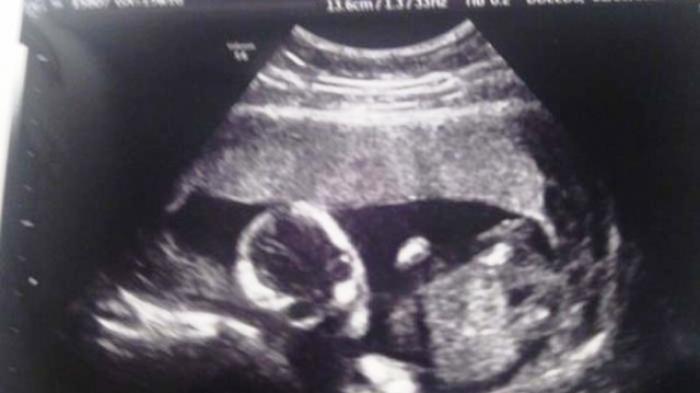

Seiring dengan kemajuan teknologi, kini adapula perangkat USG 4D. Menghasilkan gambar lebih jelas bahkan jika posisinya tepat, jenis kelamin pun bisa dilihat. Sementara teknologi sebelumnya yakni USG konvensional hanya menyajikan gambar hitam putih saja. Kadang juga sulit dipahami oleh awam. Hingga tak heran kerap kali menimbulkan persepsi lain dimata orang awam.

Nah anda penasaran dengan hasil USG lainnya? Simak bagaimana dengan foto-foto hasil USG berikut ini. Bagaimanakah anda mempersepsikannya? Benar-benar terlihat sebagai janin atau justru mirip sesuatu yang lain?

2. Penampakan janin aneh (Tumblr/bellusmalus)